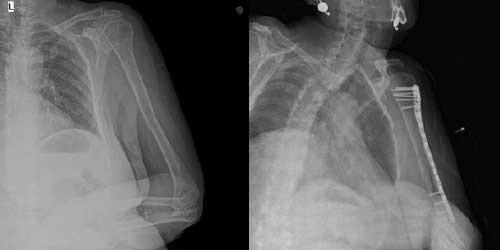

Omurga metastazı, kanserin ilk olarak iç organlarda gelişip daha sonra omurga kemiklerine yayılması sonucu oluşan bir durumdur. Çoğunlukla kan yoluyla sıçrayan bu tür metastaz, hastalarda sırt ve bel ağrısı gibi şikayetlerle kendini gösterir. Erken teşhis ve uygun tedavi yöntemleri, hastaların yaşam kalitesini artırmada kritik bir rol oynar.

Tedavide başarıyı artıran en önemli etkenlerden biri ameliyat öncesi iyi bir hazırlık ve cerrahi planlama yapmaktır. Her şeyden önce tanı doğru konmalı. Bunun için hasta iyi dinlenip, detaylı muayene edildikten sonra tetkikleri dikkatli incelenmelidir.

Her ameliyatın olduğu gibi kemik ve yumuşak doku tümör ameliyatlarının da riskleri vardır. Bu riskleri genel ve yapılan ameliyata özgü olmak üzere kabaca iki başlık halinde gruplandırabiliriz. Öncelikle anestezi ile ilgili risklerin anestezi uzmanı tarafından (...)

Ameliyat sonrası takip ve kontrol hastanın ameliyat masasında uyanması ile başlar. Özellikle damar ve veya siniri ilgilendiren ameliyatlarda hasta ameliyat masasından alınmadan ekstremitenin dolaşımı ve ilgili sinirin fonksiyonu kontrol edilir.